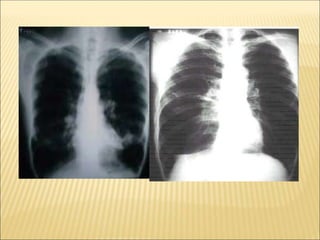

PADRÃO RADIOLÓGICO

• imagem de padrão alveolar do tipo consolidação com

broncograma aéreo, unilateral;

• imagens alveolares sem caracterização completa de consolidação;

• imagens intersticiais, reticulares ou reticulonodulares uni ou

bilaterais.

- RX SEMPRE ASSOCIADO COM QUADRO CLÍNICO.

- ajuda na definição da gravidade do quadro - envolvimento

multilobar e principalmente bilateral se associa à maior gravidade.

- presença de derrame pleural pode também significar maior

gravidade, principalmente quando de grande volume ou quando

associada a persistência de febre apesar do uso de antibióticos,

pensar na possibilidade de empiema pleural.

PADRÕES RADIOLÓGICOS PRINCIPAIS NAS

PNEUMONIAS

 Padrão intersticial: espessamento peribrônquico e infiltrado

intersticial difuso, hiperinsuflação, mais sugestivo de infecção viral

(ou asma).

 Padrão alveolar: condensações lobares ou segmentares,

especialmente quando associado a pneumatoceles, derrame ou

abscesso, sugere fortemente etiologia bacteriana.

PNEUMONIA SEGMENTAR

PN. PNEUMOCÓCICA

PN. ESTAFILOCÓCICA